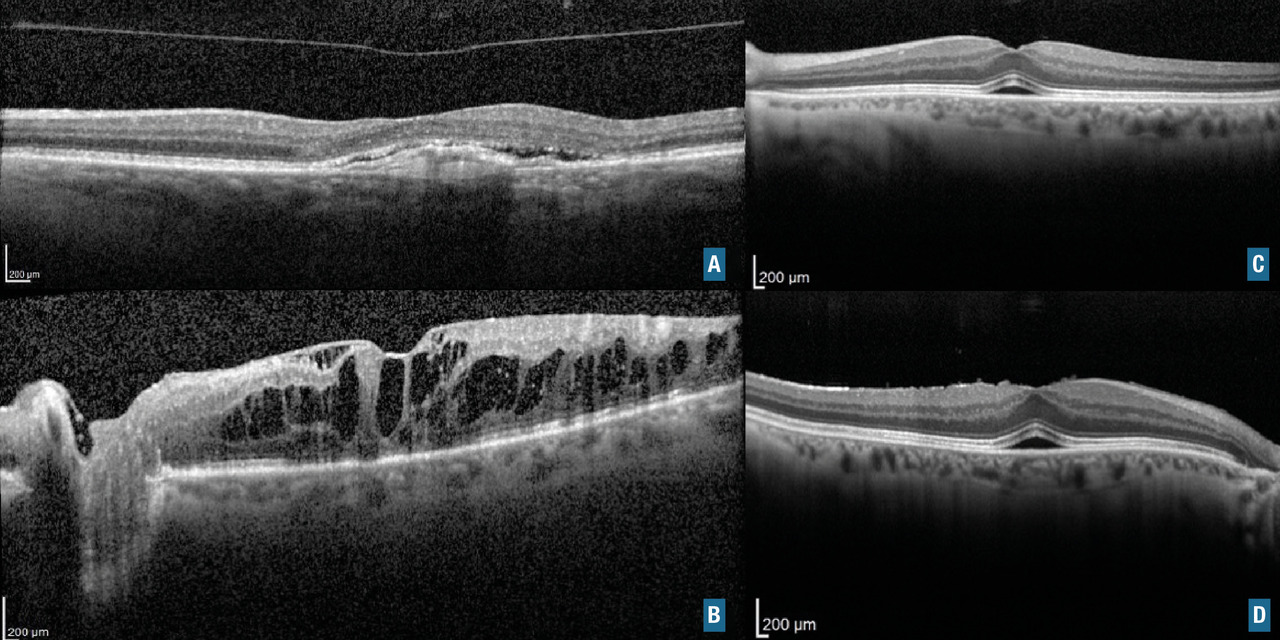

Le diagnostic est le plus souvent posé par l’OCT, avec la présence d’un néovaisseau choroïdien sous rétinien et une activité exsudative avec décollement séreux rétinien. La présence du néovaisseau est initialement confirmée par l’angiographie (fluorescéine ou indocyanine) et l'OCT-angiographie selon le type de néovaisseau (fig. 10A).

L’œdème maculaire est une cause fréquente de baisse d’acuité visuelle progressive (fig. 10B).

Maculopathie aux inhibiteurs de MEK

Les inhibiteurs de MEK agissent sur des voies intracellulaires appelées voie MAPK. Ils sont de plus en plus utilisés en oncologie, notamment dans la prise en charge des mélanomes métastatiques. Les symptômes oculaires surviennent souvent de manière rapidement progressive. L’atteinte rétinienne la plus fréquente se traduit par l’apparition spontanée de plusieurs décollements séreux rétiniens (fig. 10C et D). Ils sont généralement réversibles à l’arrêt du traitement. Parfois, selon la balance bénéfices-risques, on peut décider de poursuivre le traitement sous surveillance.